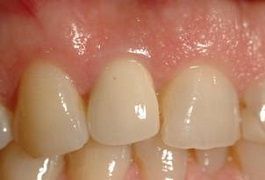

Gli impianti dentari rappresentano la tecnica più innovativa per la sostituzione dei denti mancanti. Sono simili a viti in titanio che, con un intervento piccolo e indolore eseguito con la normale anestesia del dentista, vengono inseriti dentro l'osso e vanno a rimpiazzare le radici dei denti mancanti. Sopra queste radici artificiali possono essere applicati vari dispositivi che servono a sorreggere delle corone o capsule (denti finti in porcellana), oppure attacchi a bottone che servono a stabilizzare dentiere mobili in modo da fissarle efficacemente e stabilmente. Gli impianti rappresentano una procedura molto affidabile e duratura nel tempo che consente, nella maggior parte dei casi, di non dover toccare i denti vicini a quelli mancanti, ma di far reggere in modo autonomo i denti rimpiazzati. La procedura è quella di un piccolo intervento di chirurgia orale che, in mani esperte, non comporta assolutamente alcun dolore durante e dopo l'intervento.

L'uso di impianti in "zirconio" rappresenta una soluzione molto interessante per l'estetica dei denti anteriori. Attualmente solo la parte esterna, quella visibile, viene proposta in zirconio bianco mentre la parte inserita nell'osso è sempre costituita da titanio, materiale che vanta decenni di esperienza e viene abitualmente impiegato in ortopedia. Ovviamente, durante la visita specialistica, devono essere valutati i presupposti necessari per un impianto a carico immediato, quali ad esempio l'assenza di infezione nella zona da trattare e la presenza di una buona densità ossea che consenta stabilità primaria alla "radice artificiale" ossia all'impianto. Diventa quindi fondamentale una visita da parte dell'implantologo, per discutere dei propri desideri e valutare la situazione clinica individuale.

Non sempre ogni dente necessita di un proprio impianto, ad esempio nella figura accanto possiamo vedere quattro denti sostenuti da tre soli impianti.